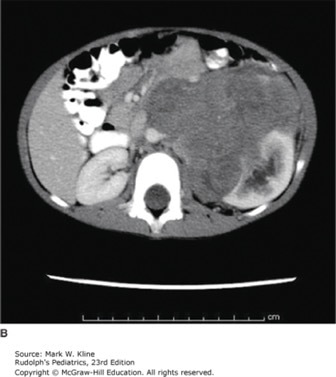

Coronal (A) and axial (B) images of child presenting with stage IV favorable histology Wilms tumor. Images demonstrate large left renal mass and massive pulmonary nodules.

Source: Kline MW. Rudolph's Pediatrics, 23rd ed. New York, NY: McGraw-Hill Education; 2018.